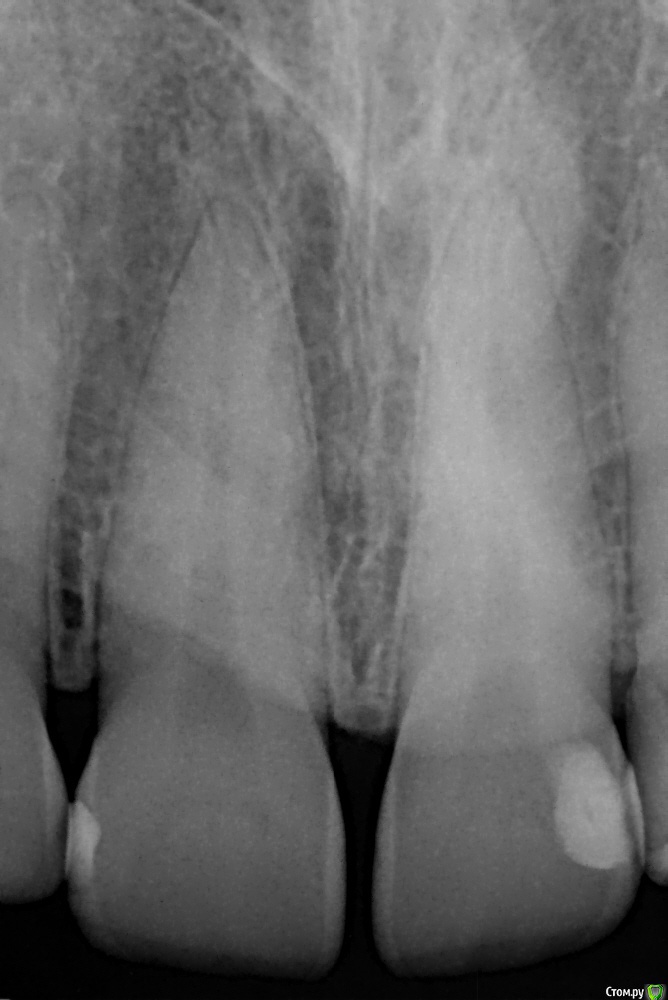

begemotik Опубликовано 15 апреля, 2017 Поделиться Опубликовано 15 апреля, 2017 (изменено) Здравствуйте. Я женщина, 36 лет. Два месяца назад закончила очередное лечение зубов. Насчет верхней правой единицы (зуб 11), где стоит маленькая пломбочка, стоматолог сказала что эта пломба стоит хорошо и заменять ее не нужно.Этот зуб ничем меня не беспокоил, кроме того что 2-3 года назад я однажды сильно погрызла шариковую ручку (обычно я не пишу от руки, так что эта привычка у меня не на постоянной основе), после этого зуб (а точнее сама челюсть в месте зуба) ныл довольно сильно около недели, потом эти ощущения полностью прошли.Сейчас меня беспокоит какое-то странное ощущение в зубе, наподобие очень-очень легкого мимолетного ноющего ощущения или даже чувства просто что ощущаю зуб (другие зубы не ощущаются). При этом откусывать твердые предметы, холодное, пить горячее не больно и никаких ощущений нет. А вот если слегка провести по зубу подушечкой пальца- какой-то странный дискомфорт. При более сильном нажатии он проходит.Подскажите, что это может быть, нужно ли снимать пломбу? Боюсь сделать хуже, центральный зуб, пломба в зоне видимости. Надеюсь, прикрепленный рентген видно Изменено 15 апреля, 2017 пользователем begemotik Ссылка на комментарий

red_butler Опубликовано 17 апреля, 2017 Поделиться Опубликовано 17 апреля, 2017 Подскажите, пожалуйста, что можно сказать по снимку? на снимке с 1.1 зубом все нормально 1 Ссылка на комментарий